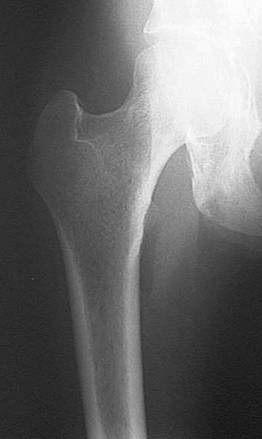

Radiografia femurului - A-P

Pacientul in DD membrele inferioare in extensie cu genunchii lipiti.

RC perpendiculara pe caseta, cade pe mijlocul coapsei (a femurului). Film de 15x40 cm, in lung; marginea proximala a casetei depaseste marele trohanter cu trei laturi de deget; marginea laterala si cea mediala la egala distanta de partile moi.

Distanta F-F = 1m; cu Bk.

Radiografia femurului A-P (2/3 superioare)